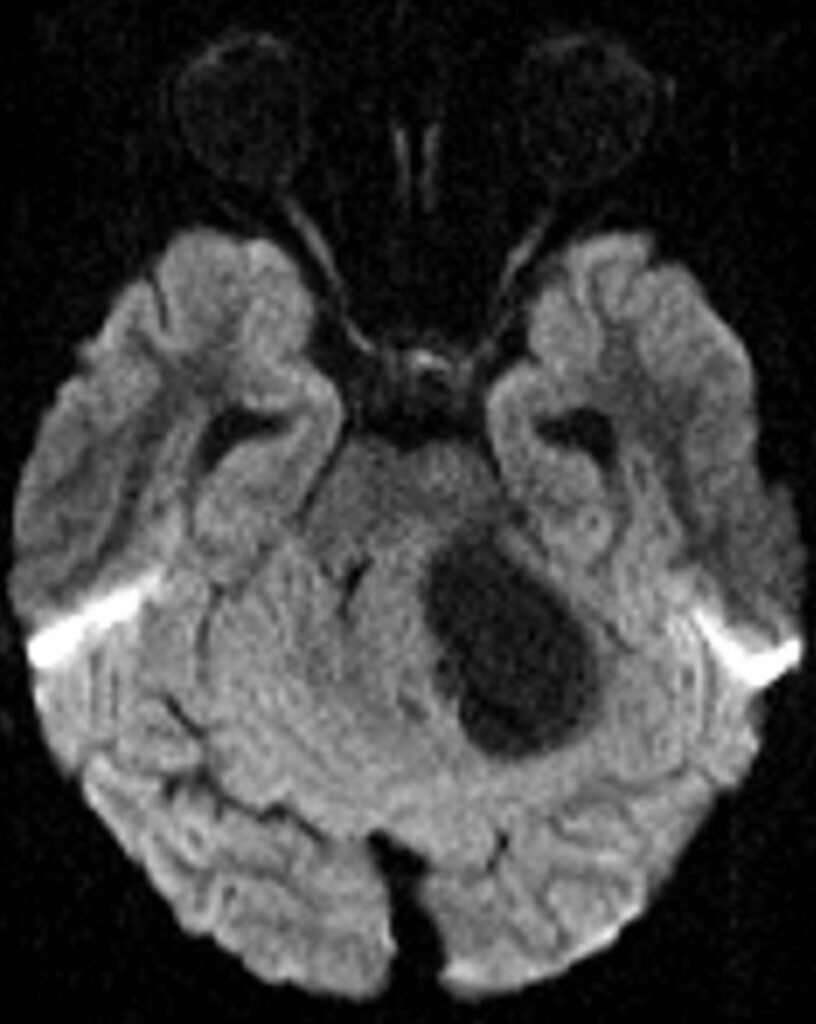

Posterior fossa pilocytic astrocytomas most often arise within the cerebellar hemispheres and are therefore lateral in location. Less commonly, they may be midline, arising from the cerebellar vermis. The classic imaging appearance is a large cystic mass with a peripheral solid nodule. More heterogeneous presentations, including a multicystic mass, predominantly solid mass with central cystic changes, or partially hemorrhagic mass, are less common [7, 17].

On MRI, the cystic component of the tumor is often similar to CSF signal intensity on T1 and T2 sequences, with the T2-FLAIR signal being more variable, based upon internal proteinaceous content. Solid portions of the mass avidly enhance, and there may also be enhancement along the margins of the cyst wall. A helpful distinguishing feature of a pilocytic astrocytoma, compared to other posterior fossa tumors, is the lack of diffusion restriction within the solid components of the tumor [18, 19] (Fig. 2).